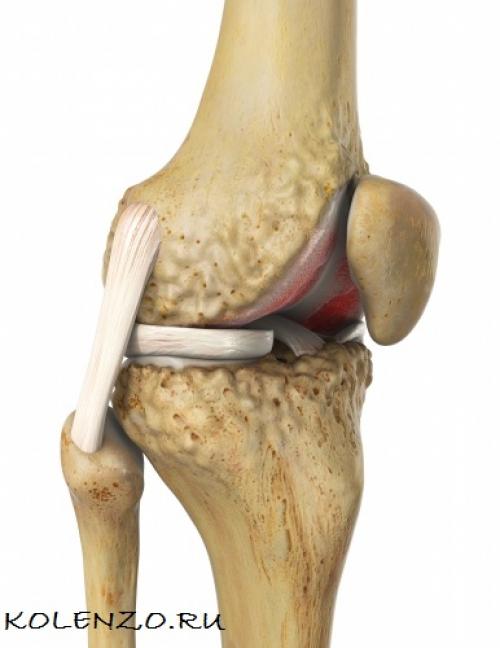

Чтобы лучше понять, почему болят колени, нужно разобраться с их анатомией. Итак, сочленение состоит из бедренной, большой берцовой кости и коленной чашечки. Две самые большие кости имеют по два выступа: внутренний и наружный мыщелки.

Все поверхности, которые соприкасаются друг с другом, покрыты гиалиновым хрящом. Благодаря ему обеспечивается подвижность коленного сустава, его амортизационные свойства. Вокруг этого соединения костей находится своеобразная капсула, изнутри выстланная синовиальным слоем. Она наполнена, благодаря которой производится питание сочленения, обеспечивается его подвижность.

Коленный сустав состоит не только из костей. Все его элементы объединяются крестообразными и коллатеральными связками, бедренными мышцами, сухожилиями. Коленная чашечка крепится к другим элементам посредством собственной связки. Для того чтобы колено двигалось, необходимо 6 синовиальных сумок. Питание и иннервация представленного сустава осуществляется посредством нервов и кровеносных сосудов, которые размещены в мягких тканях, окружающих сустав.

Колено соединяет бедро и голень. В составе коленного сустава:

- Надколенник или коленная чашечка, расположенная спереди,

- Две крупные кости – бедренная и большеберцовая, именно их соединяет колено,

- Хрящевая прокладка – мениск, уменьшающая силу трения между этими двумя костями и обеспечивающая полноту движений в суставе,

- Суставные сумки с синовиальной мембраной, ответственной за обмен веществ, и внутрисуставной жидкостью.

Менисков в колене – два, соответственно поверхностям: внутренний и наружный. Внутренний, плотно спаянный с капсулой, занимает приблизительно 60 % поверхности большеберцовой кости. Наружный – толще и шире. Форма внутреннего – в виде буквы С, а наружного – округлая, как несомкнутое кольцо. Кроме этого, в колене – большой аппарат мышц и связок.

Оба мениска состоят из коллагеновых волокон, находящихся в тесном переплетении и расходящихся в различных направлениях. Эти волокна образуют очень прочную на разрыв ткань. И сдвинуть ее тоже очень сложно.